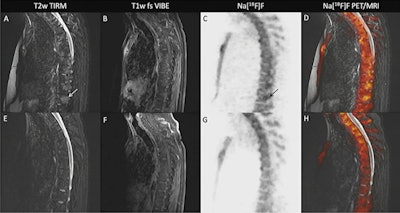

In this prospective proof-of-concept study, Bruckmann and colleagues enrolled 11 men and five women with clinically active r-axSpA to participate. The researchers performed F-18 NaF PET/MRI scans of the sacroiliac joint and whole spine in patients at baseline and at time points up to six months following the initiation of anti-TNF therapy.

A 40-year-old patient with clinically active r-AxSpA and extensive bone edema on F-18 NaF-PET/MRI at baseline and at four-month follow-up. Image courtesy of Dr. Nils-Martin Bruckmann.Three independent readers evaluated all images for inflammation (bone marrow edema) and structural lesions. F-18 NaF uptake was recorded on the level of sacroiliac joint quadrants and vertebral quadrants. The researchers analyzed a total of 128 sacroiliac joint quadrants and 920 vertebral quadrants at each time point.

At baseline, F-18 NaF uptake was found in 96% of sacroiliac joint quadrants with bone marrow edema, 94.2% of quadrants with sclerosis, and 88.3% with fat lesions. Over a mean follow-up of 4.6 months, there was a significant decrease in F-18 NaF uptake, with uptake in 65.3% of sacroiliac joint quadrants with bone marrow edema, 33.8% with sclerosis, and 24.5% with fat lesions.